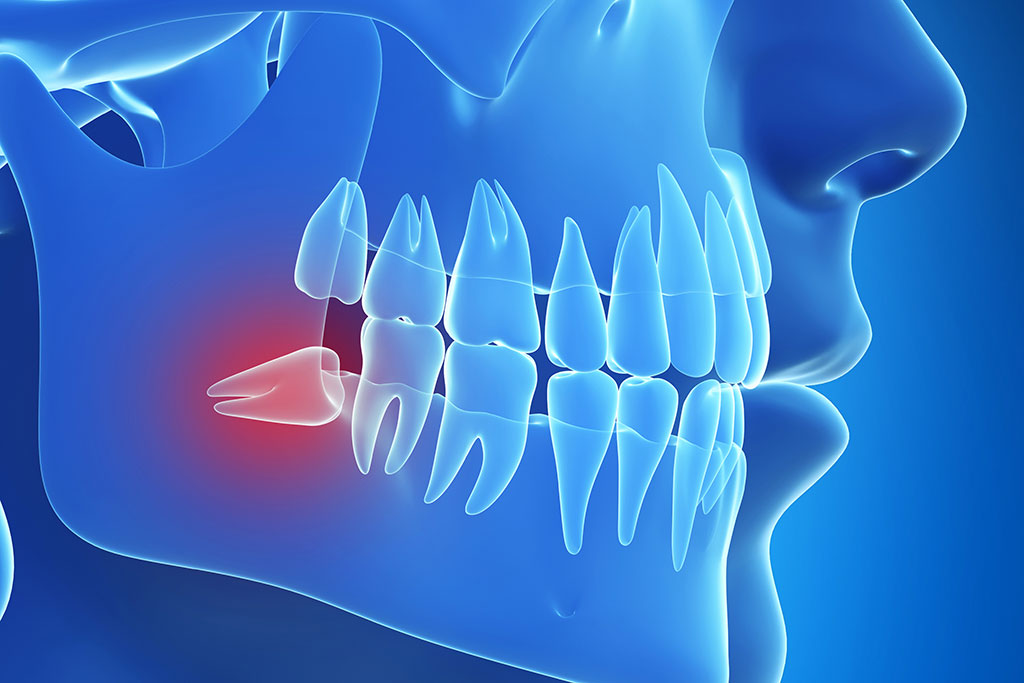

A beékelődött (impaktált), ki nem bújt bölcsességfogak az előttük levő fogakat is károsíthatják, gyulladásokat okozhatnak. A fiatalok elég nagy százalékánál a bölcsességfogak elő sem bújnak vagy aszimmetrikusan törnek elő, ami még rosszabb, mert a nehéz tisztíthatóság miatt fájdalmas panaszokat okoznak. Sok esetben a rossz pozicióban levő bölcsességfog az egész fogsoron torlódásokat okozhat.Ha a bölcsességfog nem tud vagy csak részben képes előtörni és a fenti panaszokat okozza, mindenképpen az eltávolítást javasoljuk.

A bölcsességfog eltávolítása egy rutin eljárás, aminek minimális a kockázata. Eltávolítás előtt mindig készítünk panoráma röntgent, és ha szükséges, CB-CT felvételt. A beavatkozás nem jár fájdalommal, helyi érzéstelenítésben történik.

Mikor szükséges a bölcsességfog eltávolítása?